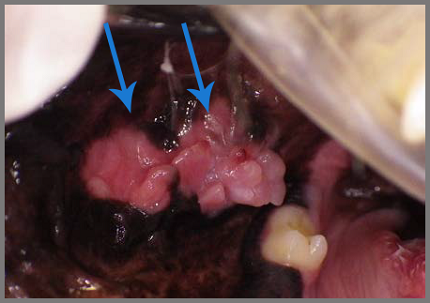

Op de foto hieronder zie je de chronische ontstekingen in het slijmvlies van de bek, door tanden en kiezen die dag in dag uit irriteren. Ook al zijn de kiezen die hiervoor verantwoordelijk zijn gezond, toch moeten ze getrokken worden om de pijnlijke ontstekingen op te lossen.